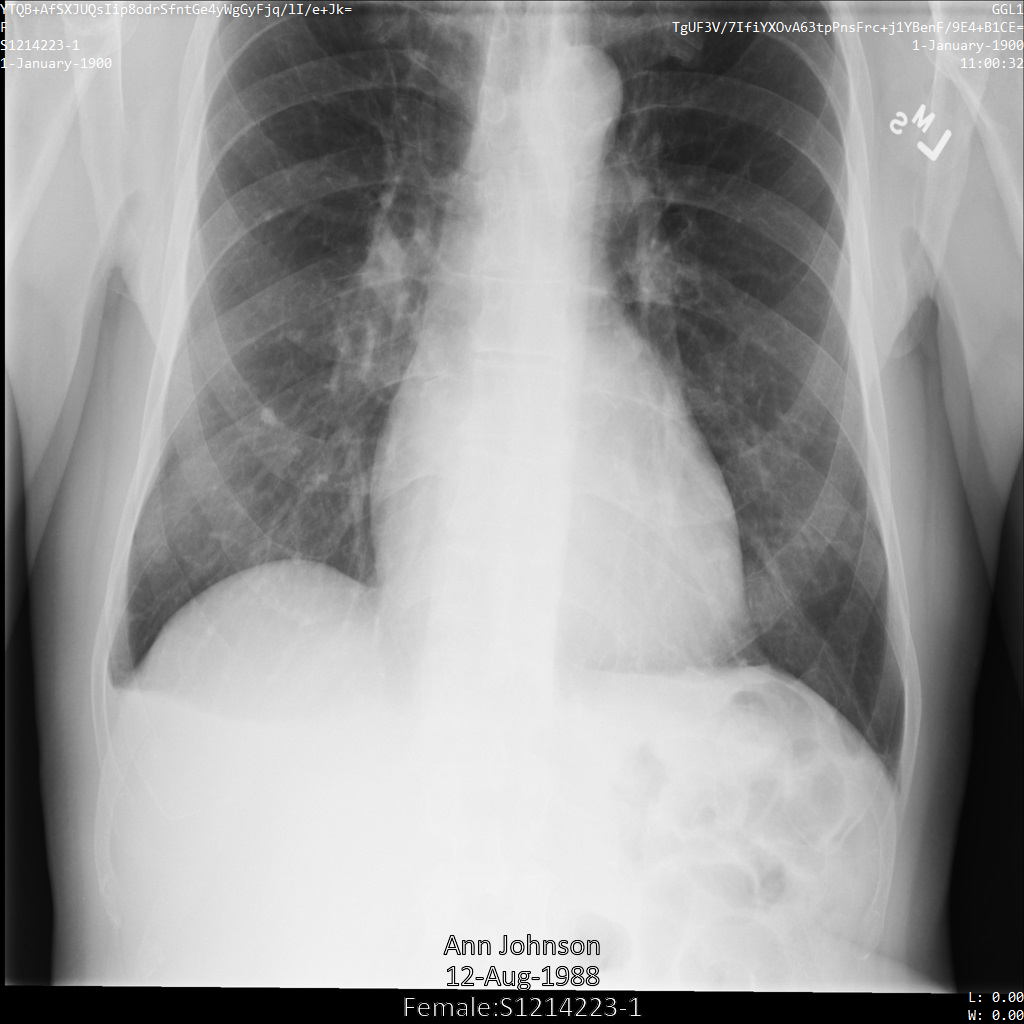

以下各部分提供的示例展示了如何使用各种方法对 DICOM 数据进行去标识化。每个示例都会提供去标识化后的图片输出。每个示例都使用以下原始图片作为其输入:

您可以将每个去标识化操作的输出图片与该原始图片进行比较,以查看该操作的效果。

使用 ATTRIBUTE_CONFIDENTIALITY_BASIC_PROFILE 标记过滤条件配置文件将图片提交到 Cloud Healthcare API 后,图片显示如下。虽然图片顶部角落显示的元数据已被遮盖,但图片底部的烧屏 PHI 仍会保留。如需一并移除烧屏文字,请参阅遮盖图片中的烧屏文字。